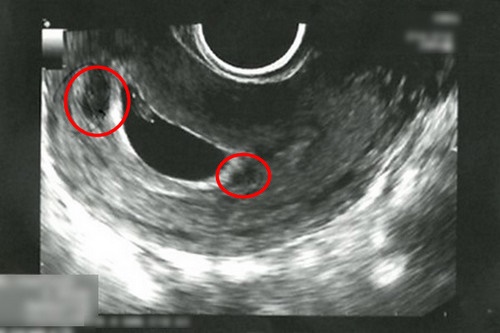

左圖:陳女士懷孕第六週,透過超音波檢查發現子宮腔內出現血塊(紅圈處)。

右圖:經過一週的中醫住院治療,子宮腔內血塊已消失,且胎兒順利成長。